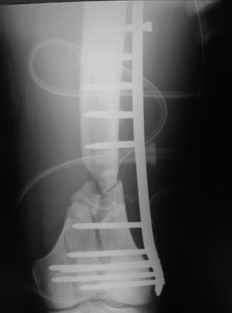

Отправитель: Zsolt Balogh 31 Октябрь 2004, 12:13

This is what we have done... As generally true for LISS look at the bone not the hardware.

There are two more srews above. The one not completely in got damaged head.